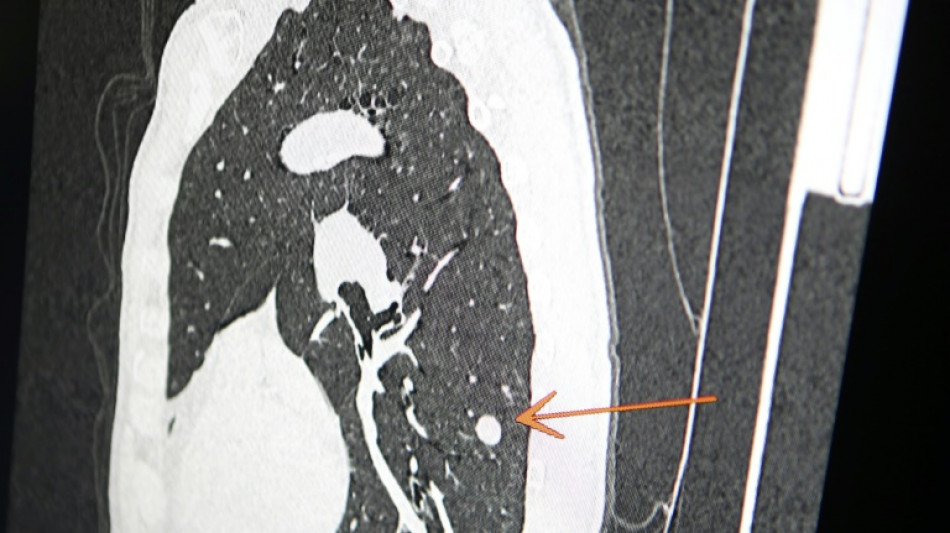

"Usted tiene cáncer", mensaje erróneo y aterrador a cientos de pacientes de una clínica en Inglaterra

Una clínica del norte de Inglaterra dio un gran susto a cientos de pacientes al enviar el mensaje "diagnóstico: cáncer de pulmón agresivo con metástasis" en lugar de sus buenos deseos de Navidad, informó el diario The Sun el jueves.

El 23 de diciembre a las 15H49, los pacientes de este centro de salud de Askern, cerca de la ciudad de Doncaster, recibieron un mensaje de texto en su teléfono informándoles de este diagnóstico, pidiéndoles que rellenaran los formularios correspondientes y concluyendo: "Gracias".

A las 16H11, seguía otro mensaje para presentar "sinceras disculpas. Esto le fue enviado por error. Nuestro mensaje debería haber sido el siguiente: les deseamos una Feliz Navidad y un feliz Año Nuevo".

Según The Sun, entre los destinatarios del mensaje figuraba Chris Reed, un padre de familia de 57 años, que esperaba resultados de análisis para determinar si padecía cáncer de pulmón.